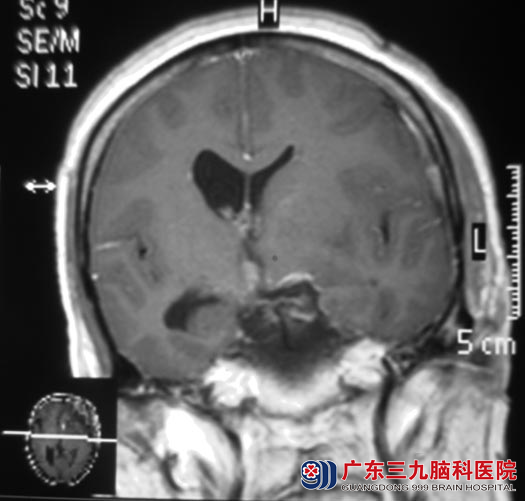

头颅MR检查提示:鞍上与鞍旁左侧示一不规则形状囊实性占位性病变,大小约45.5mm×32.1mm×35.8mm,考虑颅咽管瘤,中度脑积水。

完善相关检查后,由鲁明主任主刀,在全麻下行鞍区颅咽管瘤切除术,术中见囊实性黄白色肿瘤组织位于鞍区向鞍上生长,显微镜下分块切除肿瘤,肿瘤包绕双侧颈内动脉及其分支、与垂体柄粘连紧密,小心予以分离、切除,垂体柄保留完整,手术顺利。术后李阿姨的头痛、呕吐症状均得到改善,已康复出院。术后病理结果:颅咽管瘤。